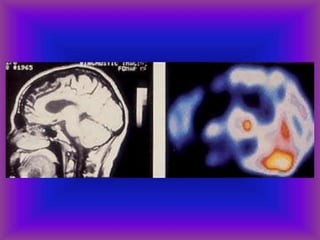

Uses for SPECT and PET

• Acute stroke

• Identify a seizure focus-increased

flow during sz and decreased

interictal flow

• Dementia-frontal pattern in FTLD,

temporo-parietal pattern in AD

• Ligand imaging in PD, others